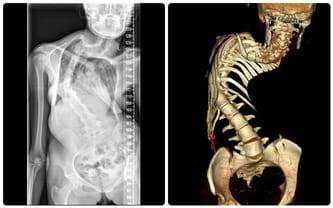

Na załączonych zdjęciach widać jak zdeformowany jest mój kręgosłup, począwszy od odcinka szyjnego do odcinka lędźwiowego.